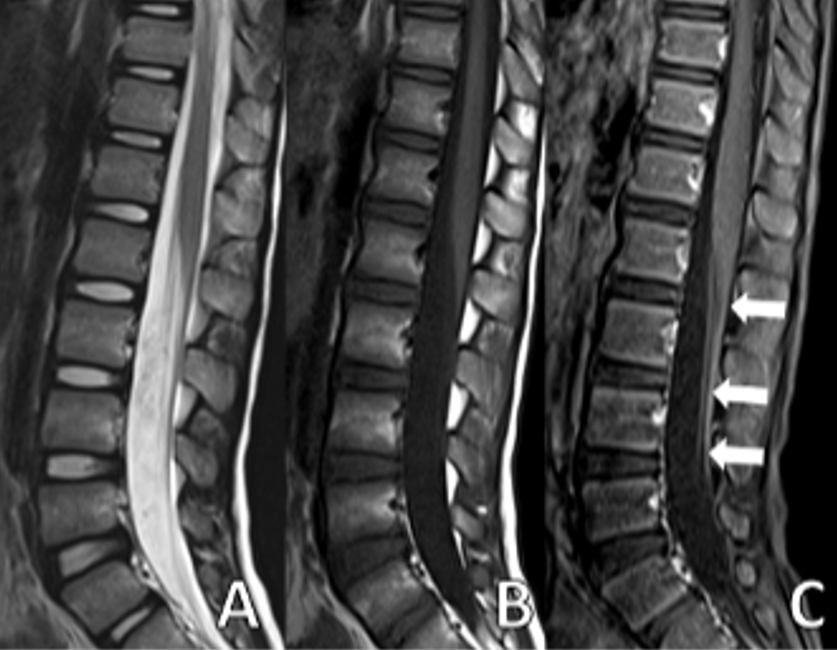

A 6-year-5-month-old male patient with no history of chronic illness presented with difficulty speaking, dyspnea, dysphagia, gait disturbance, and lower limb weakness in January 2022. He was referred to our center with those symptoms on the same day. Five days earlier, he had visited a local hospital for severe abdominal pain, nausea, and vomiting, diagnosed as acute gastroenteritis. On admission to our hospital, his vital signs were within normal limits. Neurological examination revealed no cranial nerve involvement, reduced muscle strength on both upper and lower extremities with a MRC scale of 3/5, and absent reflexes. No pathological reflexes were found. Abdominal and cremasteric superficial reflexes were intact and no sensory level was detected. Cerebellar function was assessed to be normal within the limits of the examination. CSF analysis showed an elevated level of protein (117 mg/dL). Spinal MRI showed significant contrast enhancement and thickening of the nerve roots of the cauda equina (Fig. 1 and Fig. 2).

Brain MRI: Millimeter-sized nonspecific white matter lesions. Spinal MRI: Axial T1 weighted fat-saturated image with contrast shows thickened enhancing roots of cauda equina |

All patients in this case series underwent brain and spinal MRIs. Radiological studies are essential to rule out other potential causes when nerve conduction studies and CSF examinations yield inconclusive results. An MRI of the spine is particularly helpful, as it can help exclude other conditions, such as transverse myelitis and compressive causes of polyradiculopathy. If a non-contrast MRI is performed, it is important to administer contrast media if a specific diagnosis is suspected, as the non-contrast sequences are usually normal.8 The most common site of enhancement in GBS is the anterior nerve roots, though enhancement of the posterior nerve roots can also occur.